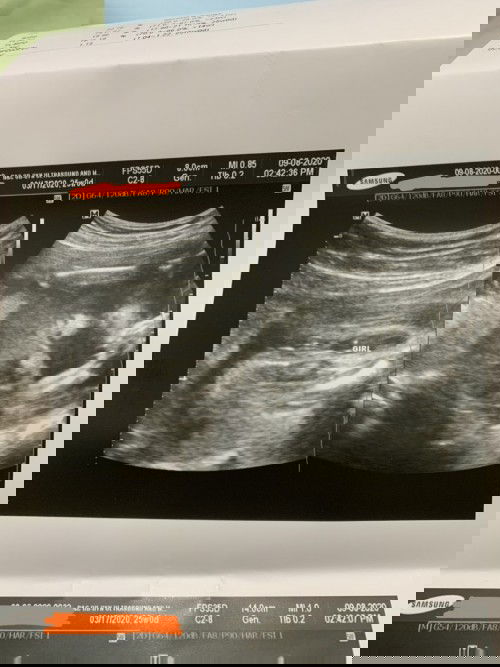

Baby Girl???

Hello mga mamsh, ask ko lang sure naba talaga na baby girl ang baby ko? I'm 25weeks now. Hindi naba mababago, I mean baka nagkamali lang ng tingin sa ultz? Balak ko na Kasi bumili Ng mga gamit Niya. :) Ty po sa sasagot.#firstbaby #1stimemom

Hamburger sign mommy. Sure na baby girl na po talaga. Congratulations! 💛